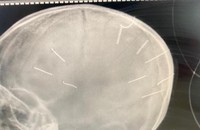

Đáng chú ý, sau khi các bác sĩ tiếp nhận bệnh nhân, tiến hành đặt ống, chụp phim đã phát hiện trên phim chụp có hình ảnh cản quang trên hộp sọ.

Qua chẩn đoán sơ bộ, bệnh nhi A. được xác định hôn mê nghi viêm màng não. Tình trạng của bệnh nhân rất nặng, tỷ lệ tử vong cao.

"Sau khi bệnh nhi nhập viện khoảng một tiếng, chúng tôi đã chuyển cháu lên Bệnh viện Đa khoa Xanh Pôn để điều trị. Bên cạnh đó, phát hiện dấu hiệu bất thường ở hộp sọ bệnh nhi nghi là dấu hiệu bạo hành, chúng tôi cũng đã báo Công an huyện Thạch Thất", ông Kiên chia sẻ.

Ông Kiên cho biết, sau khi Bệnh viện Đa khoa Xanh Pôn tiến hành chụp cắt lớp, dựng hình nhận thấy có những hình ảnh giống như đinh gỗ ở sọ và tổ chức não.